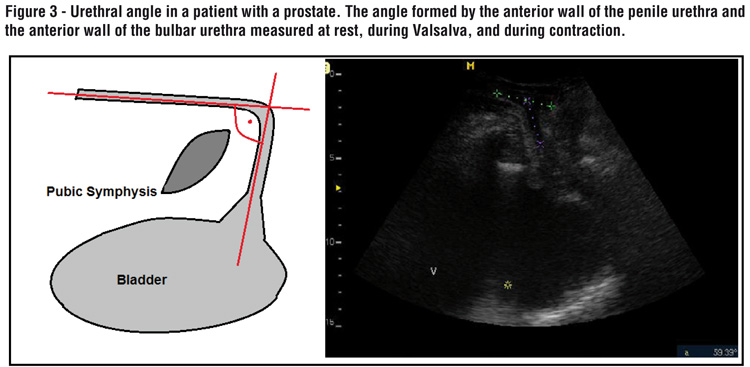

The presence of an intact prostate in control group subjects made it technically difficult to evaluate the bladder neck during the ultrasound examination. To address these challenges we added two more measurements: urethral angle and distance of the pubis. The urethral angle was defined as the angle formed by the anterior wall of the penile urethra and the anterior wall of the bulbar urethra, and was measured at rest, during Valsalva, and maximum contraction (Figure-3).